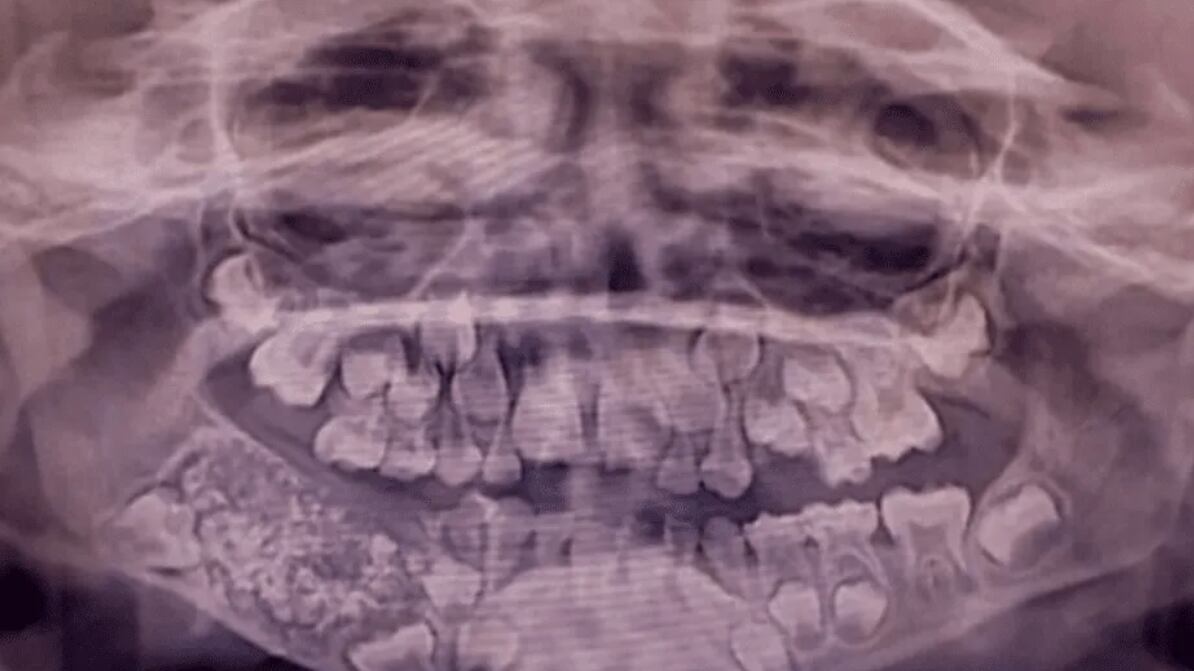

Con el tiempo, la masa continuó creciendo mientras que los dientes permanentes no brotaban en el área afectada. A los 7 años, las radiografías y tomografías revelaron una masa de aproximadamente 200 gramos alojada en la mandíbula. El Dr. Senthilnathan, responsable del Departamento de Cirugía Oral y Maxilofacial, identificó la anomalía como un “odontoma compuesto”, una variante benigna de tumor directamente relacionada con el desarrollo dental.

Durante la intervención, los cirujanos extrajeron una bolsa que contenía 526 dientes de dimensiones variables, desde apenas 0,1 milímetros hasta 15 milímetros de longitud. El proceso de clasificación y contabilización de cada pieza dental requirió cinco horas adicionales de trabajo meticuloso en el laboratorio.